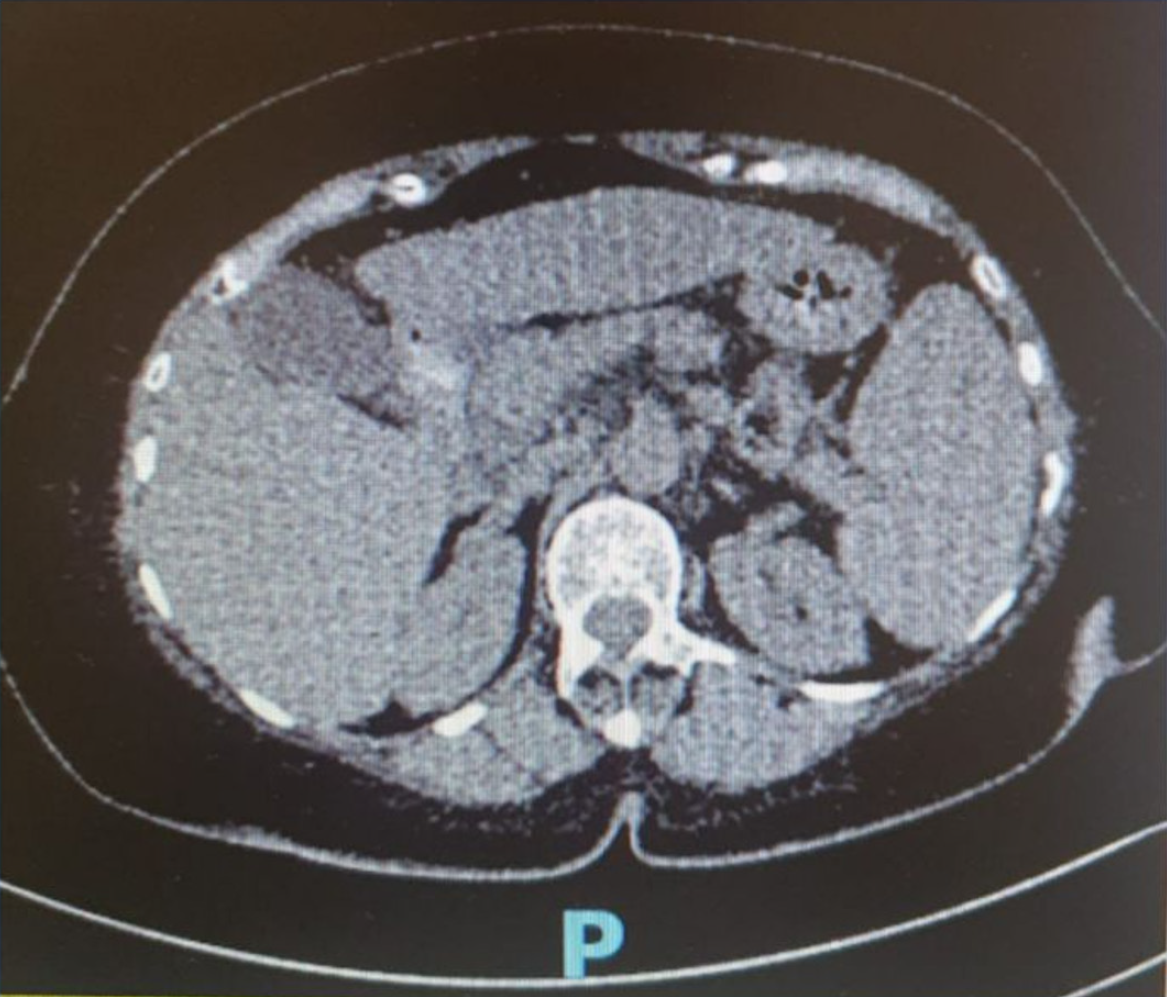

Figure 2 Abdominal computed tomography scan demonstrating moderate diffuse hepatic steatosis, splenic vein dilation, splenomegaly and multiple gallstones with mild cholecystitis.